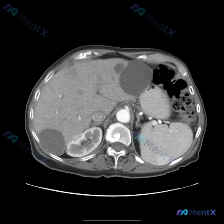

脾脏巨大囊性占位伴边缘钙化:别只盯着包虫病,这个更常见但风险同样高

看到一张腹部CT的影像资料,焦点在脾脏,整理了一下读片和分析思路,分享给大家。 先看影像核心发现 这是一张上腹部CT横断面软组织窗: - 肝脏:实质密度基本正常,未见明确弥漫性病变或实性占位。 - 脾脏:形态明显失常,内部可见一个巨大的类圆形囊性占位,占据了脾脏大部分体积。 - 关键细节:病变内部是...